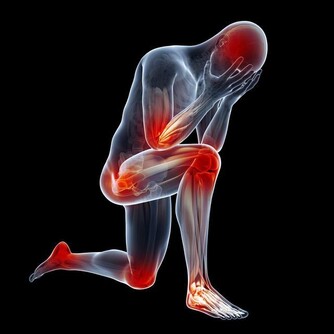

3、手腳發麻、腫脹

如果長期感覺腿部麻木、有腫脹感,也並非是其他疾病所引起的,那麼或是血栓流入動脈所致。

當血栓形成堵塞血管之後,這一部分的肌肉就會出現缺血,皮膚也會變得蒼白,體溫下降,摸起來冰涼冰涼的。時間久了,腿部容易出現腫脹,嚴重的還會伴有疼痛。